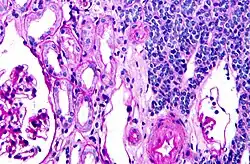

Micrograph of a metanephric adenoma with structures reminiscent of those seen in papillary renal cell carcinoma. H&E stain. | |

Metanephric adenoma (MA) is a rare, benign tumour of the kidney, that can have a microscopic appearance similar to a nephroblastoma (Wilms tumours),[1] or a papillary renal cell carcinoma.

Metanephric adenoma is diagnosed histologically. The tumours can be located at upper pole, lower pole and mid-hilar region of the kidney; they are well circumscribed but unencapsulated, tan pink, with possible cystic and hemorrhagic foci. They show a uniform architecture of closely packed acinar or tubular structures of mature and bland appearance with scanty interposed stroma.[3][4][5][6][7] Cells are small with dark staining nuclei and inconspicuous nucleoli. Blastema is absent whereas calcospherites may be present. Glomeruloid figures are a striking finding, reminiscent of early fetal metenephric tissue. The lumen of the acini may contain otherwise epithelial infoldings or fibrillary material but it is quite often empty. Mitoses are conspicuously absent.[3][4][5][6][7] In the series reported by Jones et al. tumour cells were reactive for Leu7 in 3 cases of 5, to vimentine in 4 of 6, to cytocheratin in 2 of 6, to epithelial membrane antigen in 1 of 6 cases and muscle specific antigen in 1 of 6.[5] Olgac et al. found that intense and diffuse immunoreactivity for alpha-methylacyl-CoA racemase (AMACR) is useful in differentiating renal cell carcinoma from MA but a panel including AMACR, CK7 and CD57 is better in this differential diagnosis.[8] Differential diagnosis may be quite difficult indeed as exemplified by the three malignancies initially diagnosed as MA that later metastasized, in the report by Pins et al.[9]